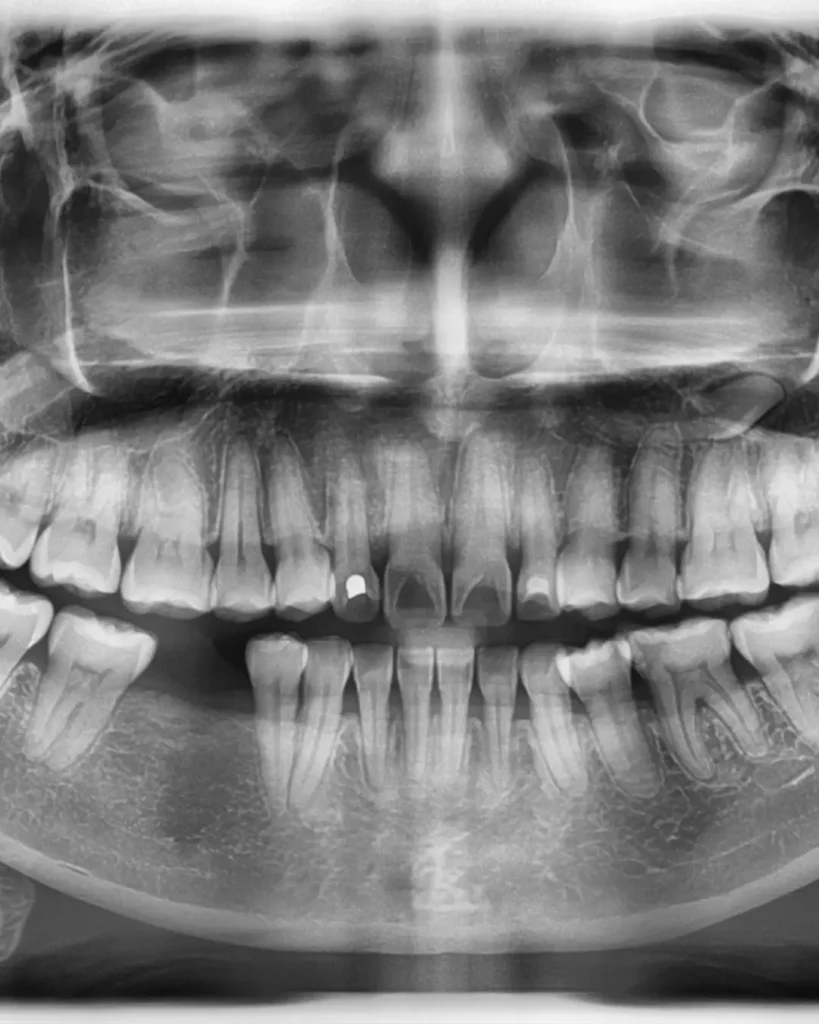

As we get older, it’s natural for teeth and gums to face new challenges. Enamel wears down, teeth can shift or crack, and gum recession exposes sensitive areas. Cavities often form in places that were never a problem before, and bone loss in the jaw can sneak up without symptoms. That’s why regular exams and X-rays are key — they reveal hidden issues early and keep your smile strong for years to come. 🦷✨